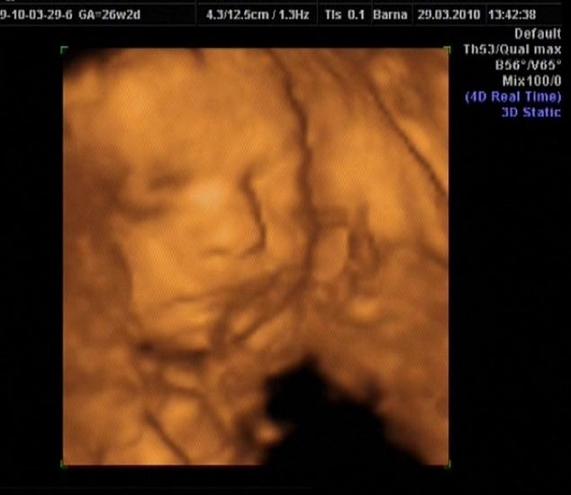

Mi is megjöttünk a második, egyben terveink szerinti utolsó 4d-s uh-ról.

. A mi kicsi fiunk jól megtréfált minket, ahhoz képest, hogy kint a váróban még szétrugdosta a belsőmet, mikor néztük, alig akart megmozdulni.

A két kicsi keze végig össze volt kulcsolva a tarkóján, ezt nem sikerült elszedni onnan, akárhogyan is próbálkozott az uh-s néni. A pici lábai pedig szinte végig az arcocskája előtt voltak, néha engedte csak megnézni a kis pofikáját úgy Isten igazából.

Ismét megerősítést kaptunk, hogy kicsi fiú, így most már aztán 100%, hogy Máté baba lakik odabent. A méretei alapján a gép 25+3-ra számolta a korát, ami teljesen rendben van, mert naptár szerint ma vagyunk 25+2 hetesek.

A becsült súlya 780 gr és a hossza 30 cm. És ami a legeslegfontosabb, az uh-s dokinéni is azt mondta, hogy minden a lehető legnagyobb rendben, semmiféle rendellenességet nem lát.

Láttuk a kicsi veséit, a kis gyomrát, és hallottuk nagyon gyorsan verni a kis szívecskéjét!

És a doktornő szerint rám hasonlít, nem az apjára…. azt mondta általában a fiúk a mamájukra hasonlítanak. De hát ez még úgyis változik. És akkor íme néhány kép a mi kis gombócartúrunkról: